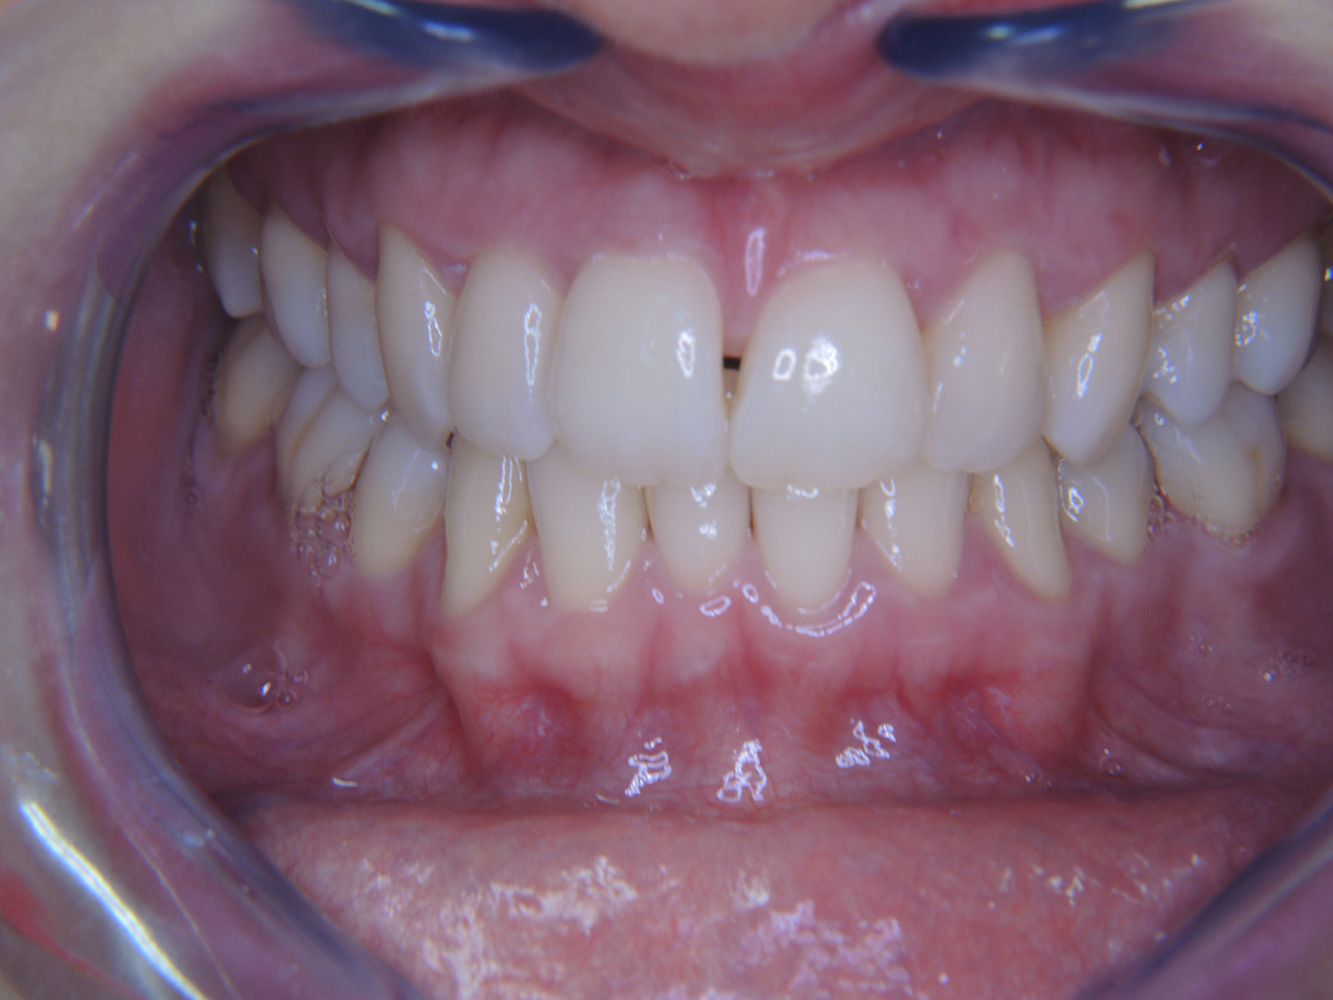

The diabetic patient with good oral health*

A 51-year old diabetic patient presents with good oral health at a prevention session. Her blood sugar levels are stable at HbA1c = 6.2%, and thus her condition is thought to be sufficiently managed with the antidiabetic drug metformin. The patient has no existing restorations or early oral disease. Using the dental results, it is possible to determine gingivitis in spite of an otherwise stable condition.

Despite the oral and general health parameters being stable, the patient’s underlying health condition requires her to attend a personalized prevention session. Diabetes mellitus is always associated with an increased risk of periodontitis (12). However, this can be controlled with good medicinal treatment. Regular monitoring of the HbA1c provides information about the course of the blood sugar level over the last eight to twelve weeks, with an HbA1c ≥ 6.5% indicating the presence of diabetes mellitus.